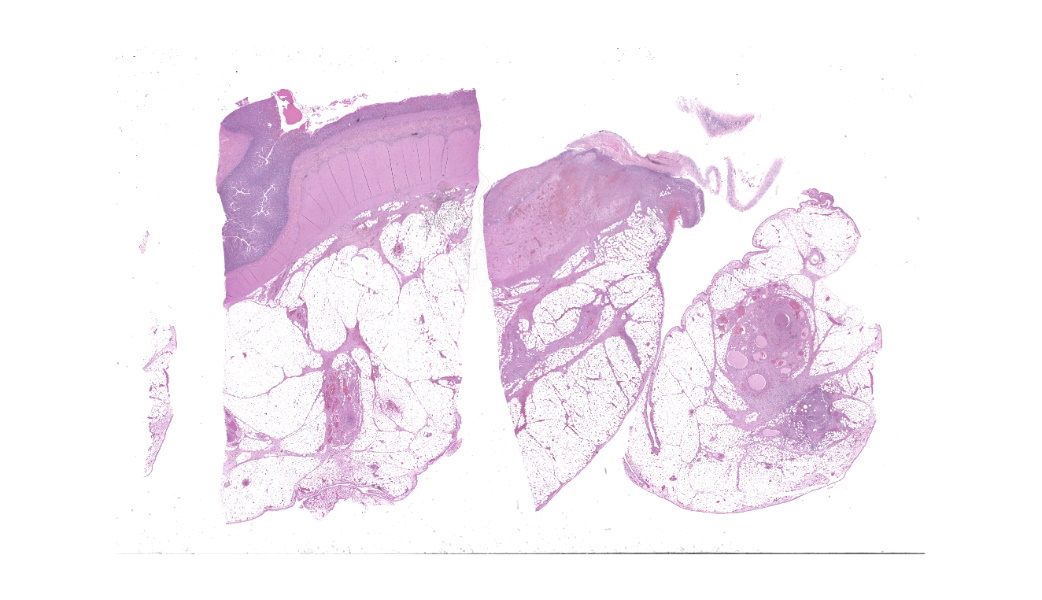

Findings are very similar in all cases that were submitted to the diagnostic laboratory.In all samples from the grossly discolored and swollen segment there was transmural necrosis of the intestine with extensive hemorrhage extending into the mesenteric fat. In the adjacent viable intestine there was eosinophilic infiltration of variable intensity. There was multifocal necrosis of mesenteric fat and, in some sections, diffuse eosinophilic infiltration. Large vessels were dilated and many contained thrombi.

Acute transmural necrotizing eosinophilic enteritis and eosinophilic peritonitis with arterial mesenteric thrombi and rare intralesional nematode larvae (spirurid)Contributor's Comment:

- Mesentery: Arteritis and periarteritis, necrotizing and eosinophilic, chronic, multifocal, severe, with arterial thrombi and rare larval spirurids.

- Small intestine: Enteritis and peritonitis, necrotizing and eosinophilic, chronic, regionally extensive, severe.